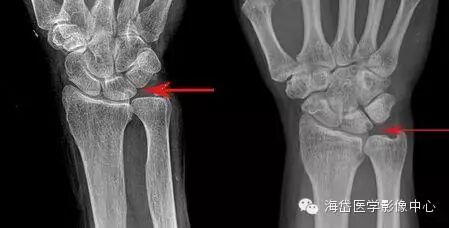

①X线:尺骨阳性变异(尺骨远端伸长)或处于中立位;月骨、三角骨坏死呈低密度小囊状改变以及月骨、三角骨关节面下软骨硬化,病变部位位于月骨尺侧近端和三角骨的腰部;尺骨小头相对关节面下软骨硬化或小囊性变。

其他X线表现包括桡骨远端骨折畸形愈合,桡骨远端异常背倾畸形和桡骨近端骨折畸形愈合导致桡骨缩短,尺桡远侧关节脱位。因为尺骨头与月骨解剖位置邻近,易发生撞击且易形成桥连状态(尺骨头与月骨连接)而产生持久性压迫,因此在尺骨阳性变异的患者中月骨发病率明显大于三角骨。

X线测量:在标准后前位X线平片测量尺骨变异,采用Gelberman等的平行线法(尺骨头关节面的平行线与乙状切迹最远端关节面的平行线之间的位置距离差)。

尺骨头长于桡骨为阳性变异; 尺骨头短于桡骨为阴性变异; 两者相等为中性变异。

对症状较重者、常规X线后前位显示尺骨变异呈阴性或中性者,采用握拳、腕旋前位摄片。